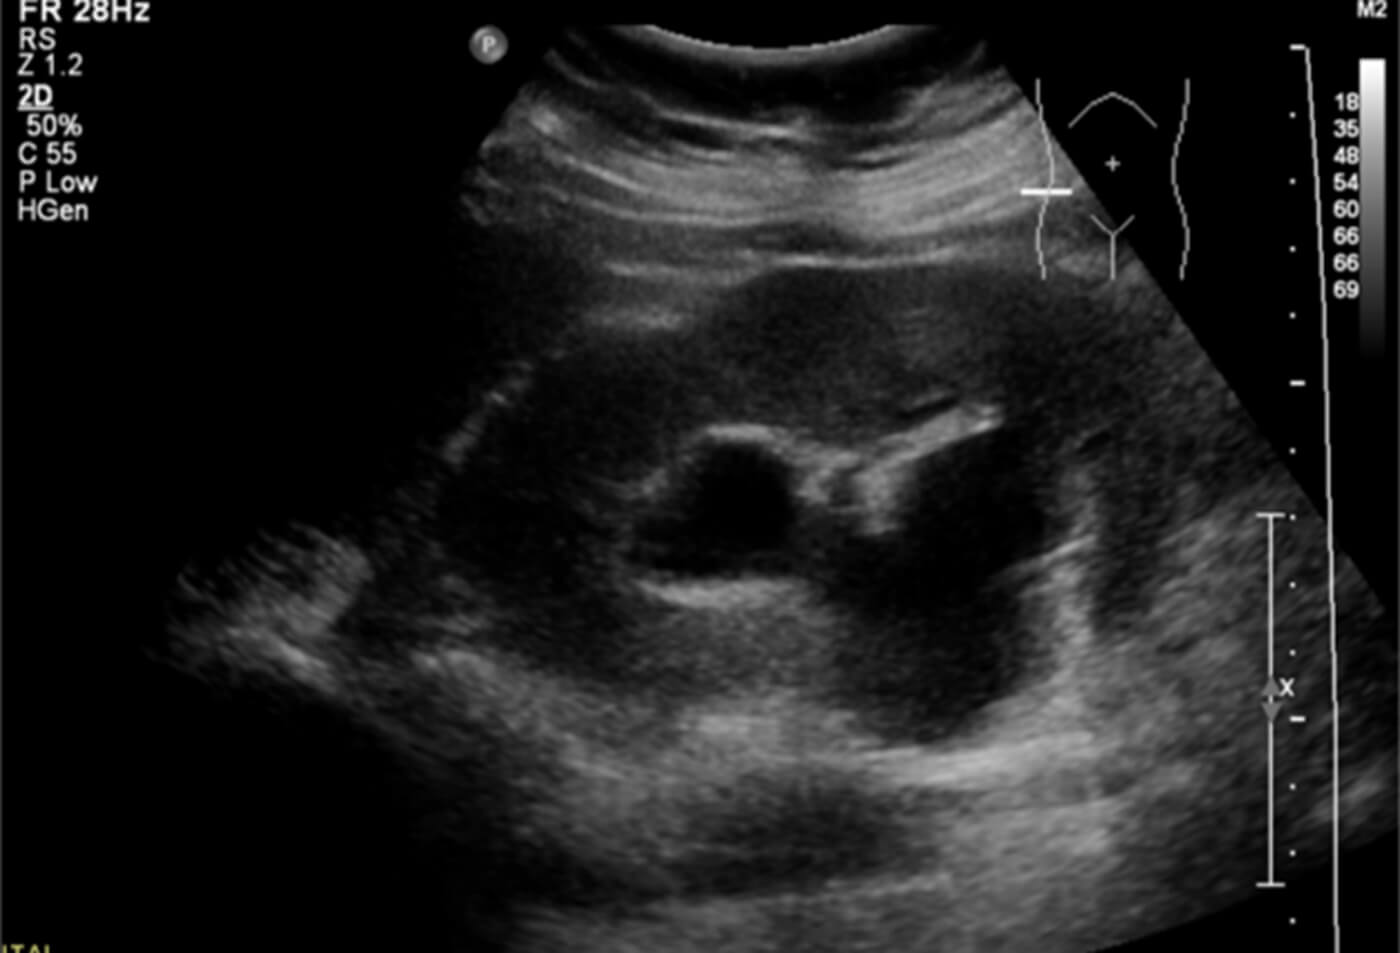

1. What does this ultrasound of the right kidney show and what does this suggest?

- Moderate hydronephrosis suggestive of stone migrating to the ureter. Physiological hydronephrosis of this extent is unusual in early pregnancy.